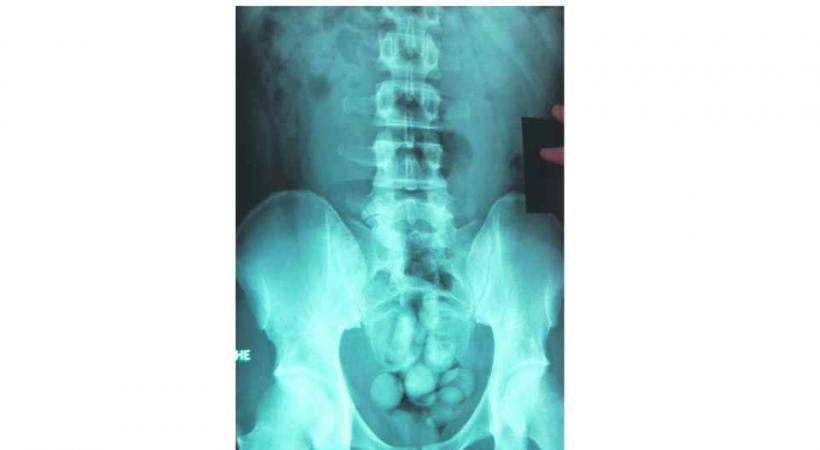

Le body packer, vous connaissez? C'est le moyen utilisé par les mules pour faire rentrer illégalement de la drogue sur notre territoire. Plus précisément, il s'agit de ces mules qui ingèrent des boulettes de cocaïne. L'Administration des douanes a annoncé avoir intercepté l'an dernier près 66 mules qui transportaient entre 60 grammes et 1,5 kilo de poudre dans le ventre alors qu'elles arrivaient principalement à l'aéroport de Cointrin: «Nous avons effectué 299 radiographies contre 161 en 2011», détaille l'adjudant Michel Bachar, porte-parole des douanes.